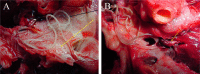

Dirofilariasis represents a zoonotic mosaic, which includes two main filarial species (Dirofilaria immitis and D. repens) that have adapted to canine, feline, and human hosts with distinct biological and clinical implications. At the same time, both D. immitis and D. repens are themselves hosts to symbiotic bacteria of the genus Wolbachia, the study of which has resulted in a profound shift in the understanding of filarial biology, the mechanisms of the pathologies that they produce in their hosts, and issues related to dirofilariasis treatment. Moreover, because dirofilariasis is a vector-borne transmitted disease, their distribution and infection rates have undergone significant modifications influenced by global climate change. Despite advances in our knowledge of D. immitis and D. repens and the pathologies that they inflict on different hosts, there are still many unknown aspects of dirofilariasis. This review is focused on human and animal dirofilariasis, including the basic morphology, biology, protein composition, and metabolism of Dirofilaria species; the climate and human behavioral factors that influence distribution dynamics; the disease pathology; the host-parasite relationship; the mechanisms involved in parasite survival; the immune response and pathogenesis; and the clinical management of human and animal infections.